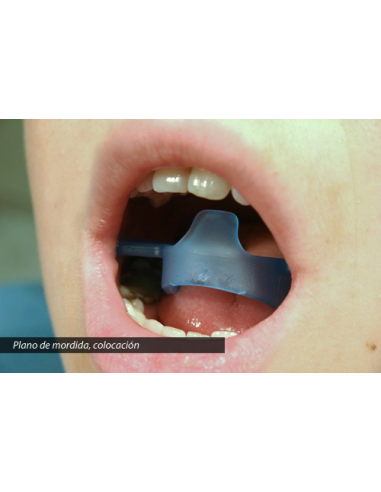

L’Otturatore Buccale Semipermeabile è un dispositivo progettato per rieducare la respirazione orale e favorire il corretto passaggio dell’aria attraverso il naso.

Agisce come una barriera parziale che limita gradualmente il flusso d’aria orale, riducendo progressivamente l’abitudine a respirare con la bocca, una delle cause più comuni di malocclusioni dentarie, recidive ortodontiche e disfunzioni oro-facciali.

La sua struttura presenta piccoli fori che permettono un passaggio d’aria controllato, evitando la sensazione di soffocamento e consentendo un adattamento naturale. Le creste periferiche stimolano inoltre la muscolatura labiale, migliorando la competenza delle labbra e il tono periorale.

L’Otturatore Buccale Permeabile rappresenta la prima fase del percorso di rieducazione della respirazione orale.

Grazie ai fori ampi, consente un passaggio d’aria moderato, permettendo al paziente di adattarsi progressivamente a respirare dal naso senza fastidio.

Questo dispositivo aiuta a normalizzare la funzione respiratoria e a ridurre l’abitudine alla respirazione orale, migliorando nel tempo la postura linguale e labiale.

Le creste periferiche favoriscono il lavoro dei muscoli delle labbra, migliorando la chiusura orale e la competenza labiale.